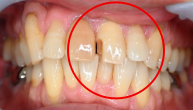

女性 Mさん 70代 (オールセラミック冠)

主訴

右前歯が動く。

治療内容

水平に破折していました。破折していた部分を取り除き、根管治療をし、ファイバーコアをいれ、オールセラミック冠を被せました。

所感

今まで、他の歯を治療した時は、すべてメタルフリーの治療をされていて、オールセラミック冠の良さを実感されていましたので、今回もオールセラミックを選択されました。

オールセラミック冠(失活歯):¥104,500(税込)

Before

破折した部分を取り除いたところ

After

根管治療後